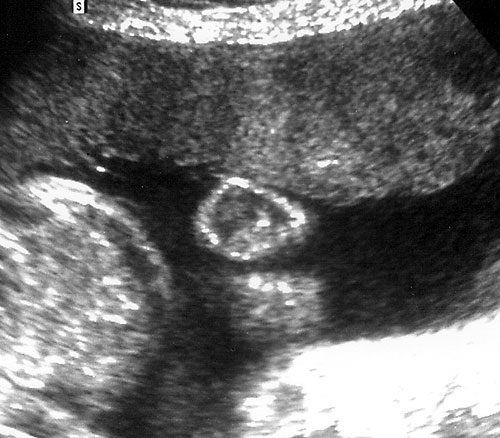

Normal fetal bladder at 18 weeks (left, at arrow). Lovely picture of both uterine arteries around normal bladder (right). This color flow picture documents the presence of the 3 vessel cord with the demonstration of the two uterine arteries coursing around the bladder. - Spine (need two perpendicular views)